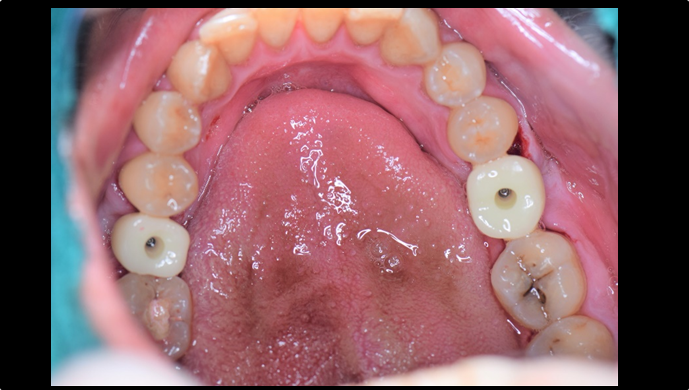

“ Immediate function recovery in the mandibular posterior with ONE-DAY implant ”

Clinical case: EImmediate implant placement & loading of #35 extraction socket with defect

- Courtesy of Dr. Kwang Bum Park, Korea -